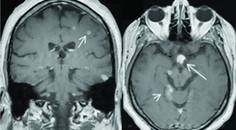

SOM fits well in the case of Ms V and is characterized by episodes of sudden-onset, rhythmic contractions of the superior oblique muscle of 1 eye leading to torsional eye movement, monocular oscillopsia, and vertical diplopia, especially on downward movement.7 Visual loss, dyschromatopsia, headaches, photophobia, periorbital swelling, and redness of the ocular surface do not occur. SOM is typically idiopathic, presumed to result from neurogenic hyperexcitability of the superior oblique muscle. In rare cases, SOM may be the result of trochlear nerve compromise at the nerve root exit zone by a superior cerebellar artery, cyst, brain tumor, or dural arteriovenous fistula (AVF).